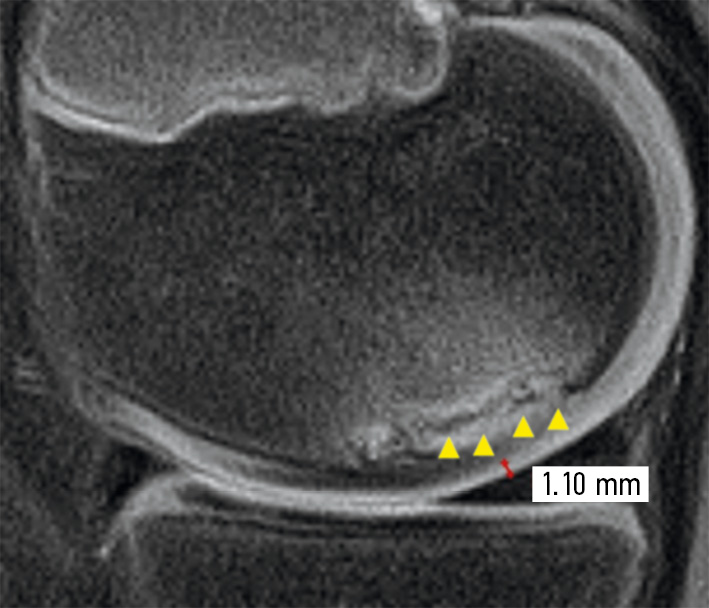

In Figure 2, the arrowheads indicate the bone zone in the osteochondral fragment in the OD lesion, which has a hyperintense coloration and is closer to the articular cartilage on a gray-black color scale. The score is 10 points.

Fig. 2. Magnetic resonance imaging of the knee joint (sagittal PD-FS image) of a child with an osteochondritis dissecans lesion. The arrowheads indicate the bone zone in the osteochondral fragment in the OD lesion. It has a hyperintense coloration and is closer to the articular cartilage on a gray-black color scale